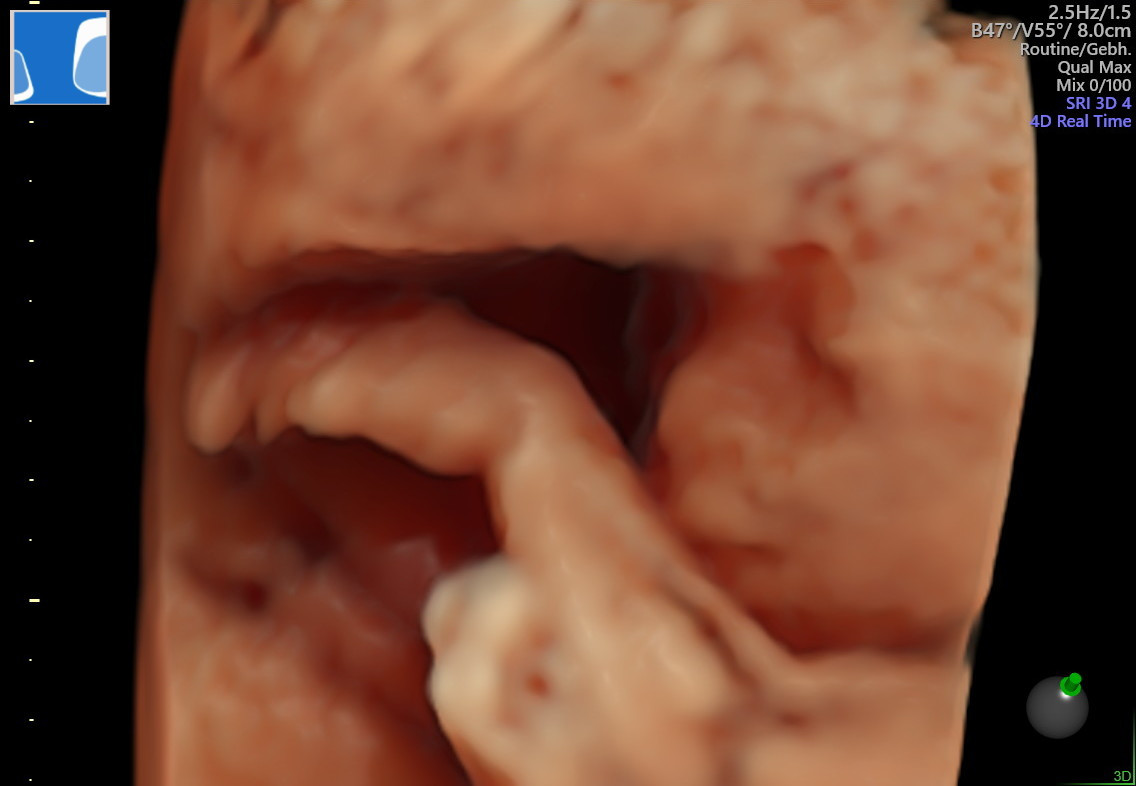

임신 5개월째 2차 기형아 검사 때쯤 되자 제법 아이의 모습이 보이기 시작했다. 엄마 뱃속에 있을 때부터 우리 아이는 움직임이 많아 초음파 때마다 애를 먹었다.